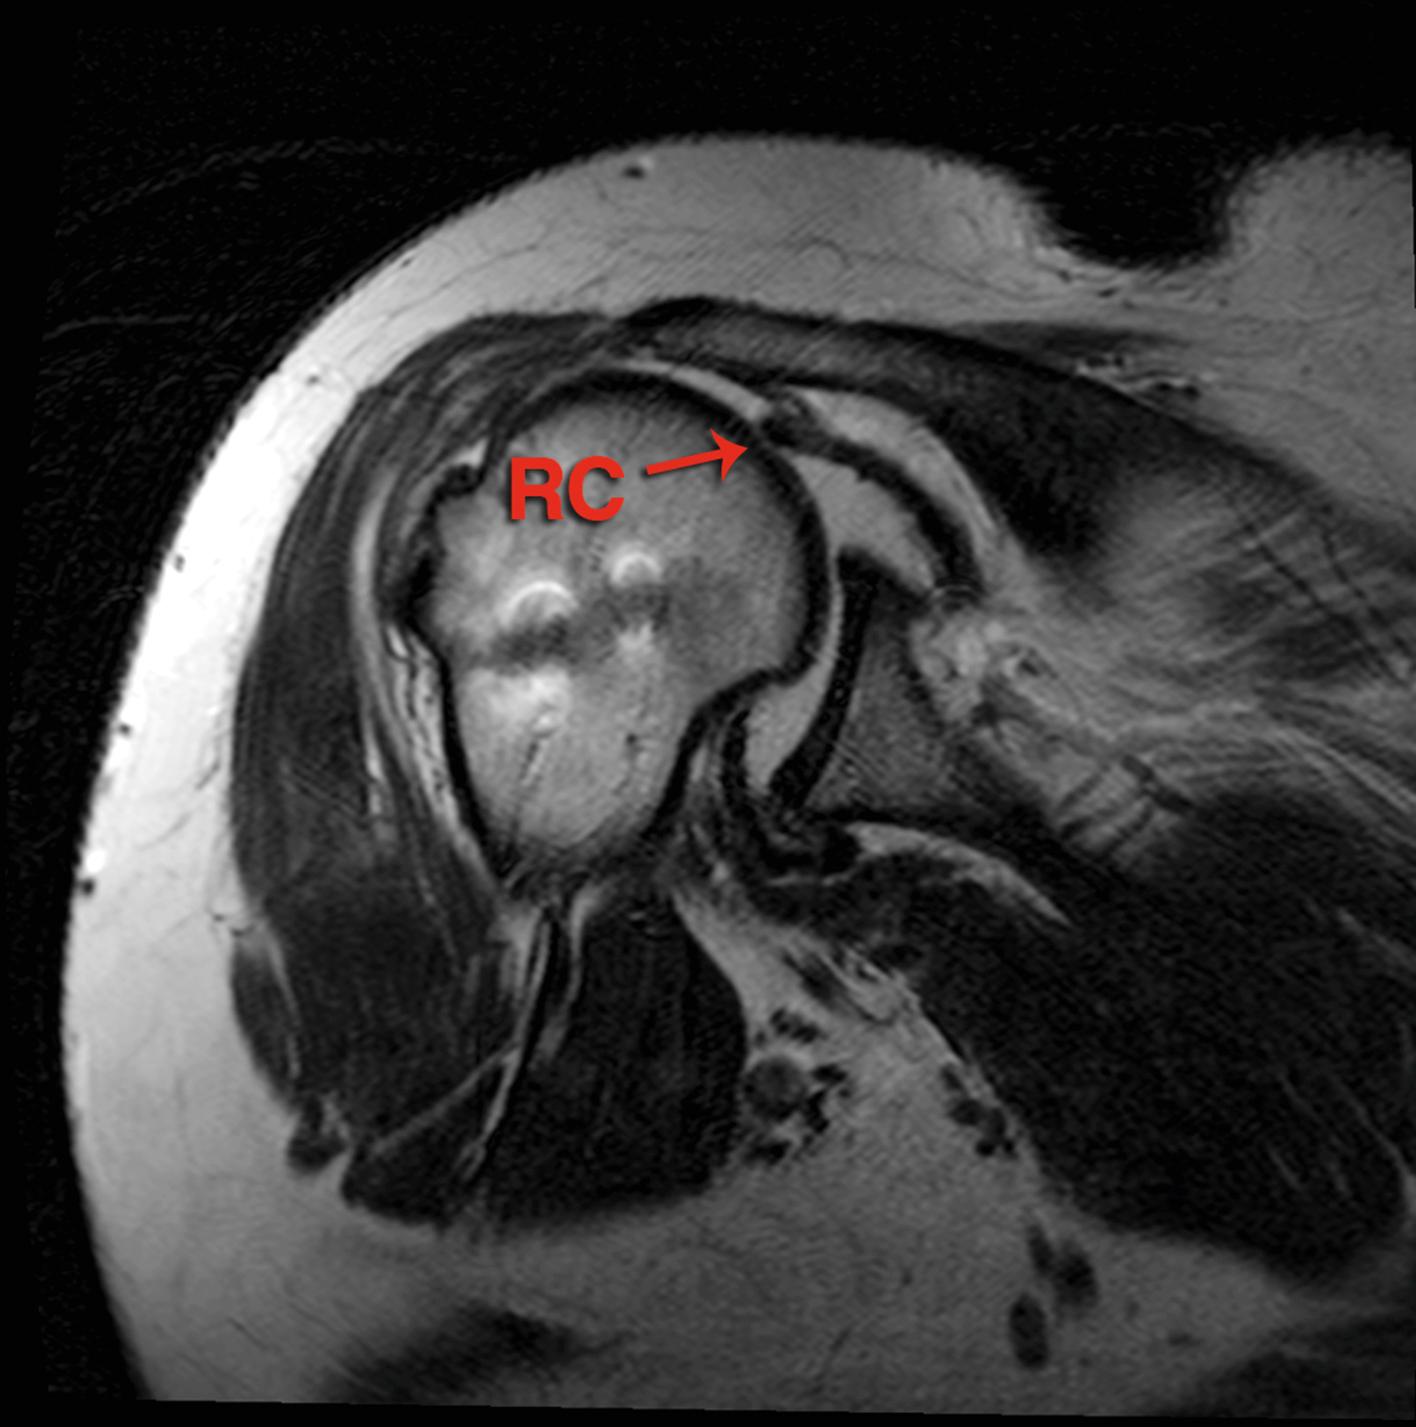

FIG. 7.2, MRI coronal view of the right shoulder with the massive cuff tear planned to undergo patch augmented repair. RC , rotators cuff.